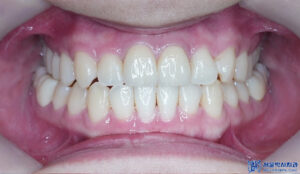

이렇게 인레이까지 진행하여

전체적인 충치치료가 마무리 되었습니다.

마무리 후 사진입니다.

결과적으로 안 아팠고 괜찮으셨다고

치료받을 만하셨다고

굉장히 안심해 주시고

만족해 주셨습니다.